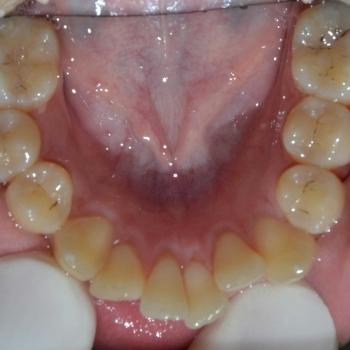

Közös döntés eredményeként fém önligírozó fogszabályozót választottunk, illetve a felső kisőrlők, illetve egy darab alsó metszőfog eltávolítására került sor. Az alsó metszőfog eltávolítása elsőre szokatlannak tűnhet, de a fogszabályozásban ez bevett gyakorlat hiszen esztétikai problémát nem okoz és a húzás által biztosított plusz hely rögtön a megfelelő helyen áll a rendelkezésünkre.

A kezelés befejeztével minden felmerülő problémát és eltérést sikerült megoldanunk, így egy funkcionálisan és esztétikailag is szép eredményt kaptunk.